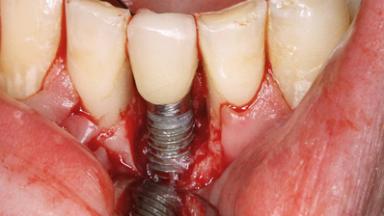

An 83-year-old man presented together with his caregiver at the dental department of the Medical University of Innsbruck, Austria with complaints of swelling in the right maxillary canine area and loss of retention of his 5-years-old mandibular denture. The patient had a significant medical history (20 years) of bipolar affective disorder with moderate depression (F 31.3) and dementia in Alzheimer’s disease (F 00.2). The patient had been in ambulant psychiatric therapy for his depressive illness for the past 20 years. He lived alone and had no children; his sister assisted with daily living. She reported that the patient exhibited compulsive hoarding behavior. In the previous two months, she had noted increasing disorientation and vertigo in the patient. She therefore accompanied him for a medical consultation at the Department of Psychiatry and Psychotherapy of the Medical University of Innsbruck. He was released home after a 6-week inpatient stay.

Type of Implants One-Piece

Attachment One-Piece